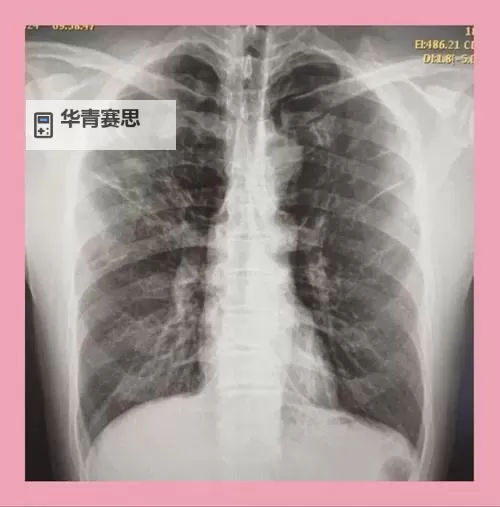

这套系统采用了最新的数字成像技术,结合高精度的探测器和智能算法,显著提升了图像的分辨率与对比度。通过精细的像素处理和优化的硬件配置,医生可以更清晰地观察到肺部、心脏等结构的微小变化。尤其在早期肺癌、结核病、间质性肺病等疾病的筛查和诊断中,这些微小的病变细节得到了更为精准的展现。此外,系统还实现了更低的辐射剂量,有效降低患者接受的辐射风险,保障了影像的安全性。

除了硬件的创新,软件方面也进行了革命性升级。基于人工智能(AI)和深度学习算法的新一代影像分析平台,能够自动识别异常区域、标注潜在病变、辅助诊断。这不仅大大减轻了放射科医生的工作负担,也提高了诊断的速度和准确率。据统计,引入AI技术后,误诊率降低了30%以上,漏诊率也得到了有效控制。这意味着在临床实践中,医生可以在更短的时间内作出更可靠的诊断决策,早期干预的可能性大大增加。